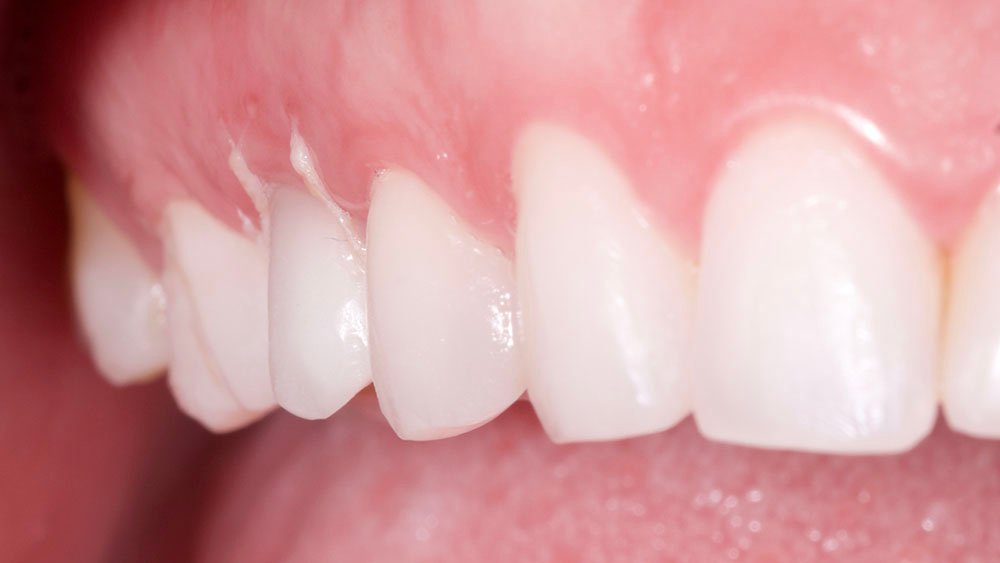

O procedimento selecionado para esse relato de caso promoveu resultados satisfatórios e melhorou a estética. No término do procedimento cirúrgico, a paciente foi orientada a tomar uma cápsula de Amoxicilina 500 mg (EMS – Germed Farmacêutica, São Paulo- Brasil) a cada 8 horas por sete dias; um comprimido de Nimesulida 100 mg (Eurofarma Laboratórios S/A, São Paulo-Brasil) a cada 12 horas por três dias; e um comprimido de Dipirona 500 mg (Sanofi Medley Farmacêutica Ltda., São Paulo-Brasil) a cada 6 horas. Além disso, foi indicado à paciente que evitasse alimentos pastosos e pegajosos, que preferisse alimentos frios ou gelados e utilizasse bolsa de gelo no local.

No acompanhamento mensal realizou-se proservação e radiografias periapicais da região para verificar a cicatrização dos tecidos e integridade do implante. Após o período de três meses, foi cimentada uma coroa definitiva de zircônia monolítica.